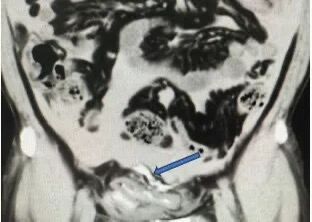

箭头处可见外渗进腹腔的造影剂 膀胱为何会“破”? 该医院泌尿外科李晟主任分析这是一个“连环效应”。一是外力撞击腹部受击时,因未戴护具,膀胱壁可能已受损。二是饮酒+憋尿随后大量饮酒,导致膀胱感觉变得迟钝,更容易长时间憋尿,使膀胱内压力持续升高。 三是膀胱破裂在原有损伤的基础上,内压超过极限,导致膀胱破裂。“必须立即手术,否则尿液持续渗入腹腔,会导致感染性腹膜炎、脓毒症,危及生命。”李主任强调。 取得患者及家属同意后,张先生被紧急送入手术室,行腹腔镜下膀胱破裂修补术。 术中发现其膀胱顶部有一长约5厘米的破口,腹腔内积存约1500毫升血性液体,肠道已被从膀胱流出的尿液浸泡。医疗团队迅速完成修补,手术顺利进行。 {jz:field.toptypename/}术后张先生恢复良好,次日即可排气排便,尿液引流正常。通过微创手术治疗,其腹壁仅留三个0.5-1cm的微小创口。经过一周住院治疗,术口已拆线,创口愈合良好,现已康复出院。 李晟副主任医师特别提醒: 下腹部遭受外力撞击后,如果伴有腹痛、排尿困难或血尿,应高度警惕膀胱损伤,立即就医。饮酒会降低膀胱敏感性,切忌长时间憋尿,否则极大增加破裂风险。 一旦确诊为外伤性膀胱破裂,绝大多数需要手术修补,同时探查有无其他脏器损伤,避免严重感染。运动或日常活动中,注意保护腹部,避免重击;饮酒后应及时排尿,切勿强忍。“记住身体异常,千万别硬扛,及时就医是关键。” 文、图/广州日报新花城记者:肖桂来 通讯员:唐迪琛 |